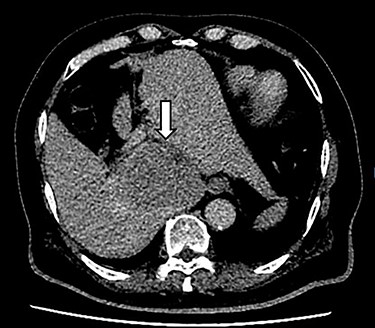

A 66-year-old male was referred to our institution for management of a liver lesion found incidentally on abdominal imaging. There was no significant past medical or surgical history, and he was asymptomatic. On physical examination, the patient was vitally stable and all systemic examinations were unremarkable. Contrast-enhanced triple phase abdominal computed tomography (CT) scan showed an arterial enhancing lesion in Segment I of liver with early washout, consistent with HCC (Fig. 1). This lesion received blood supply from the right renal artery (Fig. 2). Ultrasound-guided biopsy was performed to confirm the diagnosis of HCC, and subsequently the patient successfully underwent TACE. Figures 3 and 4 show the angiographic findings of the right renal artery branch supplying the lesion. Repeat CT scan at 6-week follow-up showed no evidence of residual disease.

CT scan axial section delayed phase showing a 3.2 × 3.0-cm lesion (arrow) with early washout in Segment I of liver, consistent with hepatocellular carcinoma.